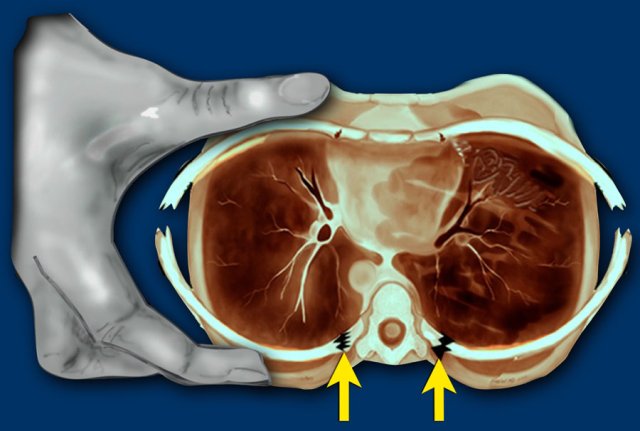

Rib fractures

In violent shaking the child is held very tightly around the chest and squeezed while being shaken.

This compresses the ribs front to back and tends to break them next to their attachment to vertebrae and laterally where they are being literally almost folded in half.

As a result of this specific trauma mechanism, lateral and posterior rib fractures are highly specific for abuse.

Cardiopulmonary resuscitation is rarely, if ever, a cause of such fractures.

These rib fractures in abused children may be found incidentally on chest X-rays performed for other reasons, such as evaluation for pneumonia.

Rib fractures are highly specific for abuse.

In a study in the Netherlands a total of 254 fractures were found in 56 cases of abusive head trauma. There was an extremely high incidence of rib fractures and metaphyseal fractures (ref).

Rib fractures pose difficulties similar to those of metaphyseal injuries in that they are easily overlooked on radiographs.

In the acute stage they are not evident on radiographs, as little displacement occurs.

They are often identified on the repeated skeletal survey when the fractures are in the healing stage showing callus.

Especially

fractures at the ventral ends of the ribs are challenging.

Ultrasonography is helpful in detecting dislocation at the ventral costo-chondral junction.

Images

Child evaluated for soft tissue mass in costchondral region. The ultrasound shows soft tissue swelling (yellow arrows), chondral part of rib (red arrow) disrupted from bony part (orange arrow) of rib. The Initial chest film was negative. Chest film 2 weeks later showed fractures.